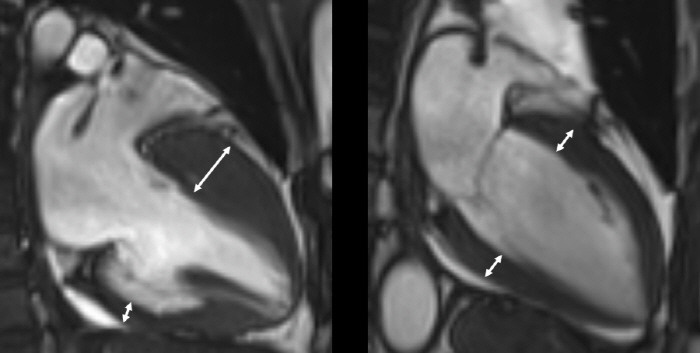

Diagnosis is made through imaging tests such as echocardiography and magnetic resonance imaging, and fibrosis is progressed in the thickened myocardium or muscle tissue is degenerated into adipose tissue. However, as there is hypertrophic cardiomyopathy without such tissue degeneration, comprehensive judgment by a specialist is important.